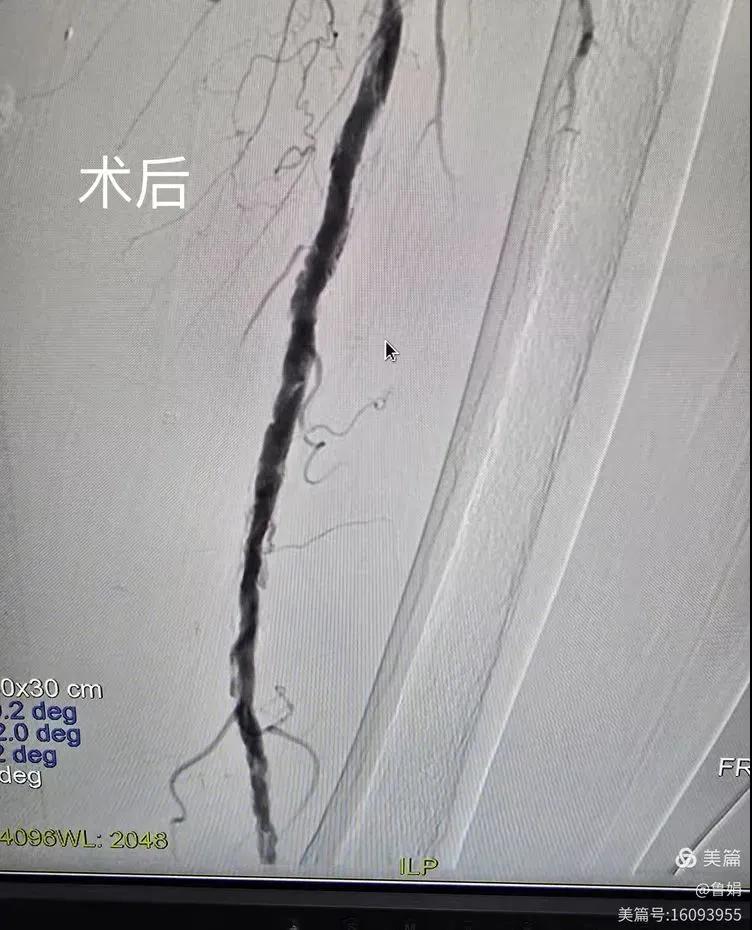

據(jù)悉,該患者,女,73歲,下肢動脈硬化閉塞癥,“以靜息痛,間歇性跛行”入院,CTA評估:股淺動脈,腘動脈間斷性多段重度狹窄,外二科血管外科團隊根據(jù)患者病情,結合檢查結果,經(jīng)過科室會診后,決定對該病人行介入治療。手術由周創(chuàng)業(yè)副主任與北大一院血管外科專家郭宏杰教授聯(lián)合開展,對股淺動脈,腘動脈重度閉塞段行血管開通+藥涂球囊擴張成形,術后狹窄明顯緩解,血流恢復!